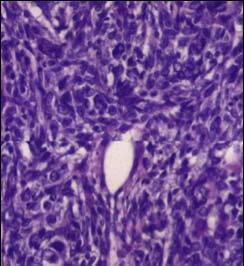

Foto 4. Patrón tipo retiforme

Foto 6. Proliferación fusocelular

FOTO 7. Área mixoide con células de Sertoli células de Leydig